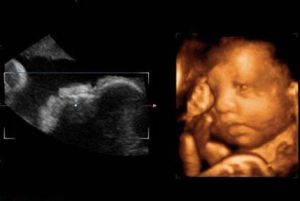

為了“小天使”的幸福和健康,行之有效的方法就是大力開展產前診斷。產前診斷又叫出生前診斷,它對胚胎或胎兒在出生前是否患有遺傳性先天畸形作出準確的判斷,對異常胎兒進行治療性流產,防止缺陷兒出生,從而保證後代健康。產前診斷僅有20多年歷史,但發展迅速,方法包括X線、胎兒鏡、超音波、生物化學及酶檢查、染色體診斷等,最常用的是超音波和染色體檢查。

B超是一項無痛無損傷方法,套用最廣,它可以對胎兒的面部、四肢、脊柱等外部發育情況進行檢測,還可直接對胎心和胎動進行動態觀察,但B超不宜做的太多,因為超音波或多或少會影響胎兒的聽覺等功能,一般在正常情況下以孕早、中和晚三次B超為宜。